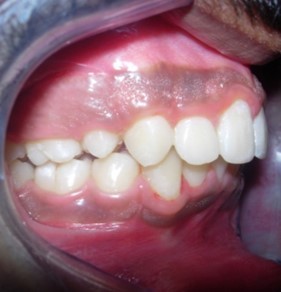

Results

The soft tissue frontal and profile improved dramatically. (Figure 7a-b). The bilateral posterior crossbite was corrected. The severe increase in overjet of about 13mm was effectively reduced to 3mm and the severe deep bite was also corrected (Figure 7c,Figure 7d). Fixed maxillary and mandibular lingual retainers were given. (Figure 7e, Figure 7f). Post orthodontic treatment, normal root inclinations of the teeth and normal alveolar bone levels was observed. (Figure 8).

Figure 7d.Post treatment intra-oral – Right

Post treatment lateral cephalometric radiograph was taken to assess the treatment changes. (Figure 9). The changes in maxilla in the anteroposterior direction was insignificant, however an increase in the length of the mandible measured from Condylion (Co) to Gnathion (Gn) and an increase in anterior facial height was observed. Maxillary incisors were retracted dramatically by 8mm and the mandibular incisors were proclined by 3mm to camouflage the skeletal class II malocclusion.(Table 1). Effective expansion of the maxillary constriction as an end-of treatment goal was achieved. (Figure 10a,Figure 10b).

The end of treatment result showed a good improvement in the transverse, anteroposterior, and vertical dimensions with markedly improved dentofacial esthetics.

A combination therapy of a banded rapid palatal expansion appliance and orthodontic treatment with pre adjusted edgewise appliance therapy was instrumental in the correction of a severe skeletal Class II malocclusion with an orthognathic maxilla and retrognathic mandible. This two-phase therapy resulted in a dramatic improvement of the facial and smile esthetics with good occlusal interdigitation that enhanced the patient’s speech, personality and self-esteem.